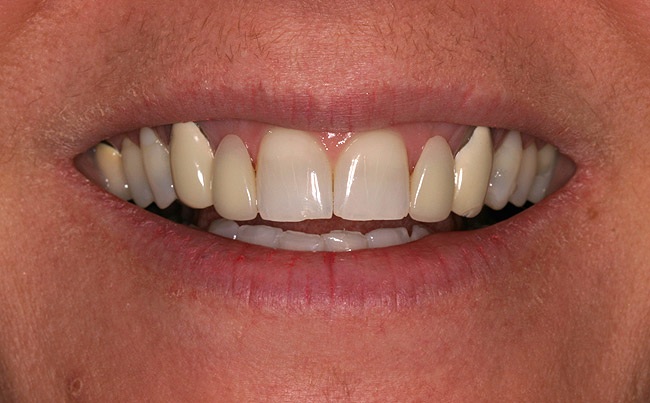

Figure 6a  Upper right central incisor, history of trauma, existing RCT and restoration unsatisfactory.

Figure 6a

Figure 6b  Upper right central incisor, history of trauma, existing RCT and restoration unsatisfactory.

Figure 6b

Figure 6c  Upper right central incisor, history of trauma, existing RCT and restoration unsatisfactory.

Figure 6c